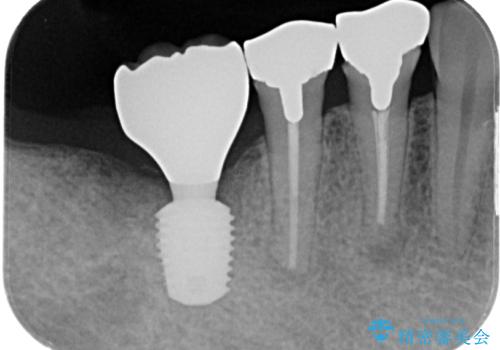

- 「歯を抜いたので、インプラントを入れてほしい」という主訴で来院された患者様です。

他院で歯根破折により抜歯をしたとのことでした。

CTにより残存骨量を確認しインプラント埋入を行っていくこととしました。

今後手前の根管治療を行っている歯が歯根破折を起こして抜歯になる可能性を想定して手前の歯に平行にインプラント埋入を行っています。

インプラント早期荷重について

インプラント早期荷重とは、通常よりも短い期間で人工の歯を装着し、早い段階で噛めるようにする治療方法です。

従来は数か月間待つ必要がありましたが、骨の状態や全身状態が良好な場合には、条件を満たせば早期に仮歯や最終の歯を入れることが可能です。